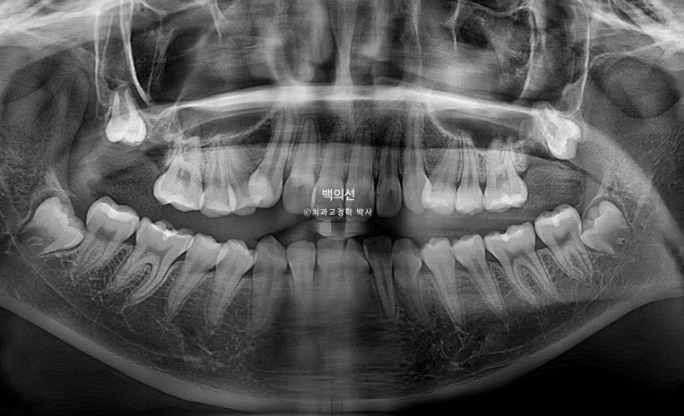

23.11

송곳니는 잡아놓고 위 어금니들을 뒤로 밀어내며 송곳니 덧니를 가지런히 만들 공간을 얻기로 합니다.

맨 뒤 큰어금니까지 뺏으니 어금니 후방이동이 수월한 편입니다.

엑스레이에서 치료시작 6개월만에 사랑니가 발치한 두번째 큰어금니 자리로 금방 내려온 것이 보입니다.

파란화살표는 발치한 맨 뒤 큰어금니 자리로 내려온 사랑니랍니다.

치료시작 6개월차 사진을 보면 큰어금니들을 뒤로 보내어 어금니 사이에 공간이 생겼습니다. 덧니를 펼 공간이 꽤 많이 만들어졌습니다.